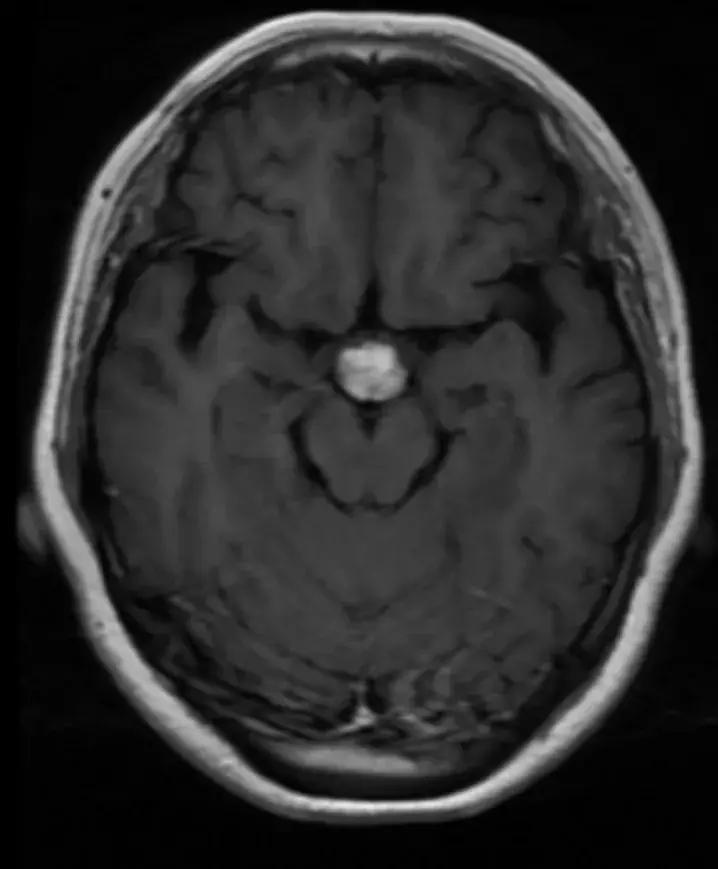

下丘脑见一类圆形异常信号灶,大小约1.6×1.4cm,T2WI呈等略高信号,T1WI呈等信号,DWI呈等信号,增强后明显异常强化,轻度压迫视交叉,FLAR见视交叉及双侧后方视束信号增高。